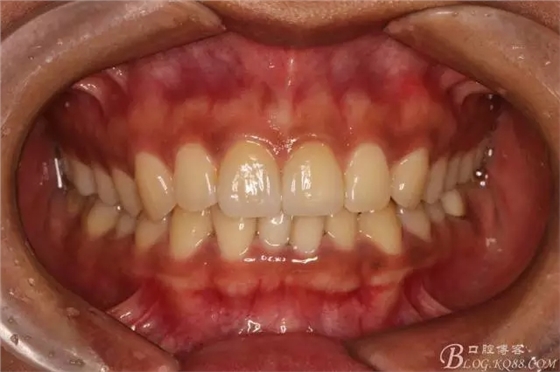

復(fù)查舌側(cè)照

本來想拍個(gè)微笑像,可惜抓拍幾張都不自然,就留了這張。(兩周復(fù)查時(shí))

半年后(2016.9)復(fù)查照(這次復(fù)查已完全適應(yīng)修復(fù)后的效果,冷熱也不敏感了,我的心也就放下了)